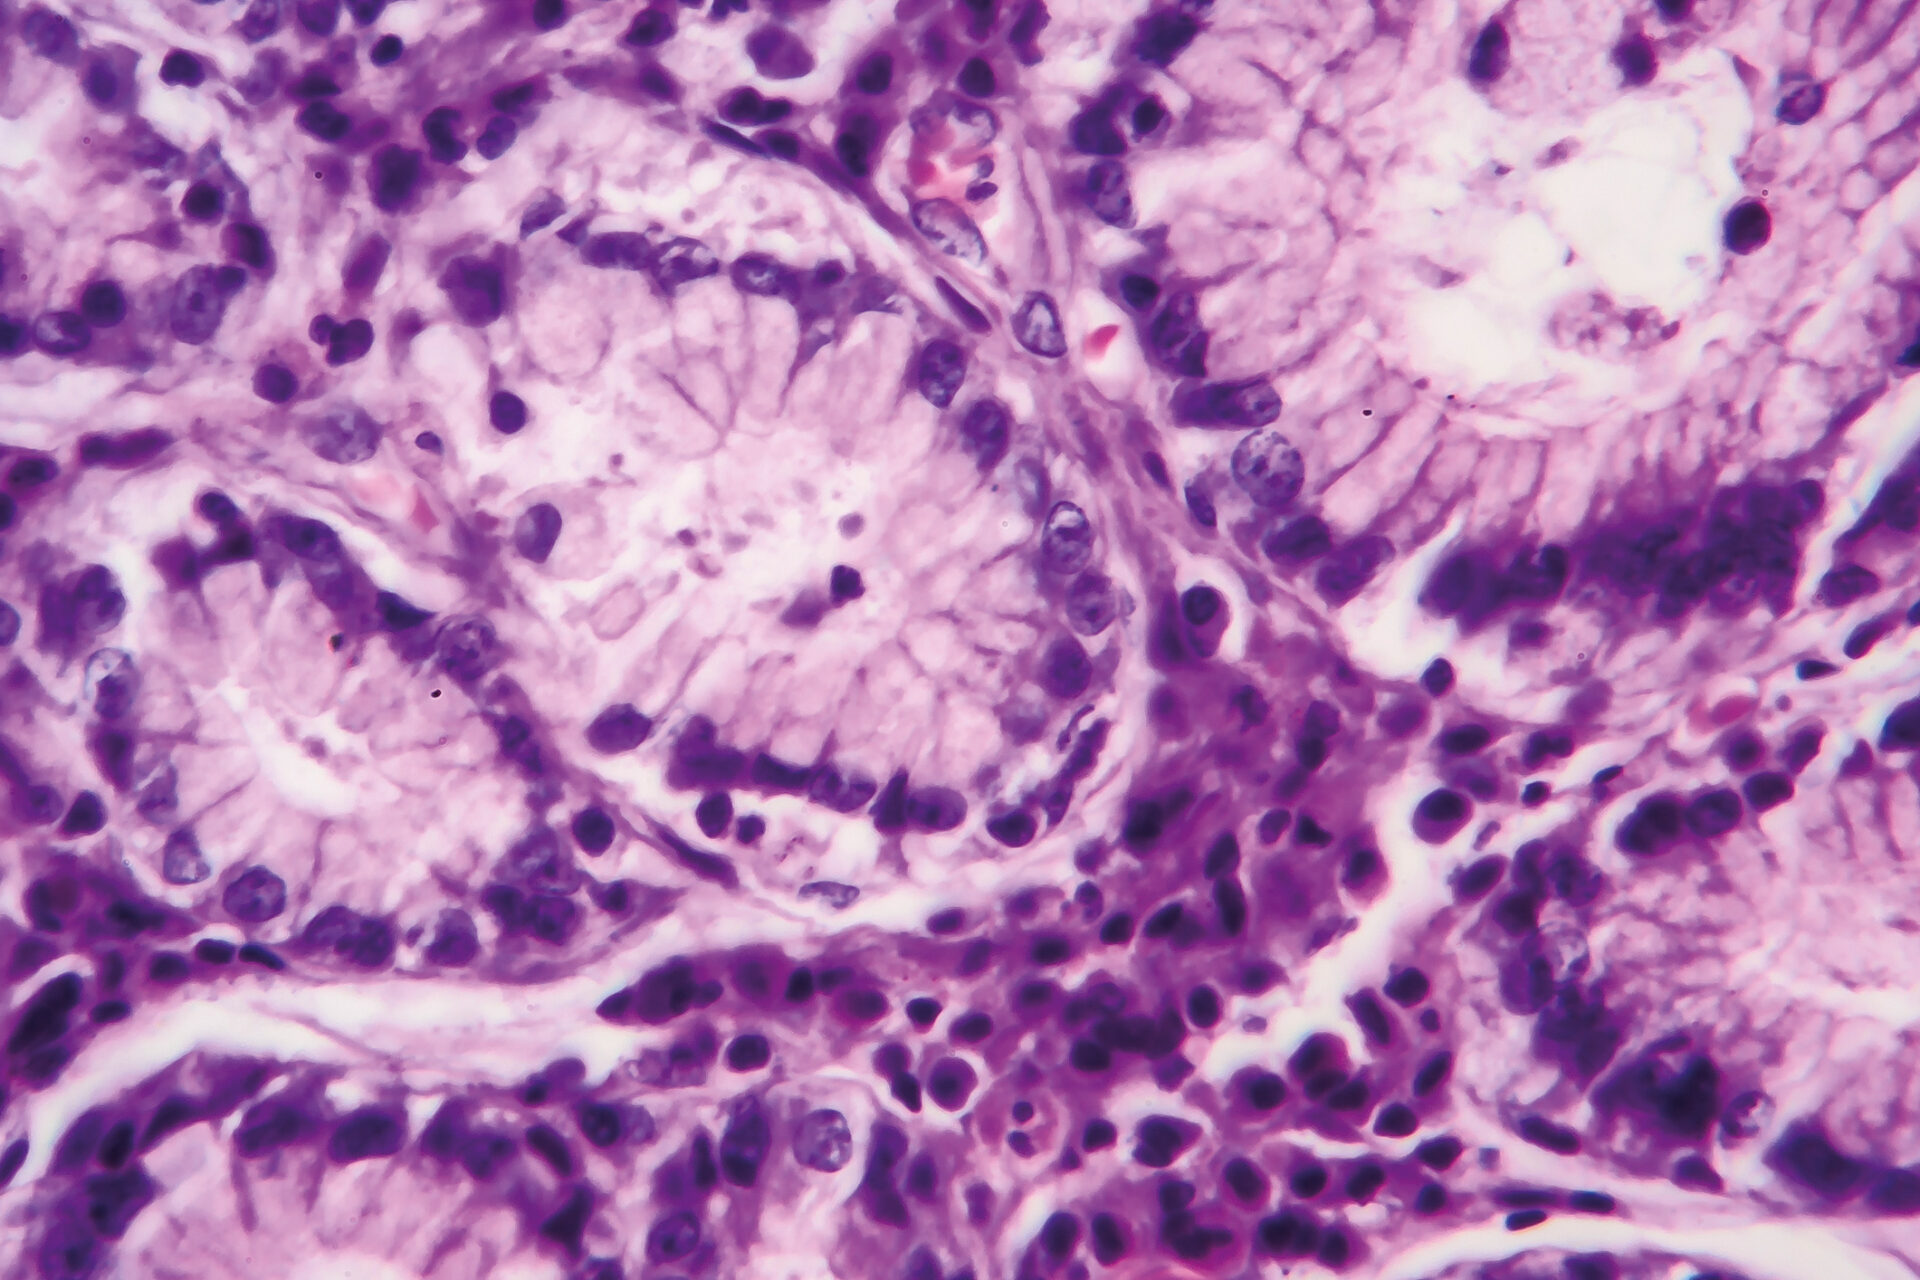

Einem Adenokarzinom des Magens kann chirurgisch unter bestimmten Voraussetzungen mittels einer distalen Magenresektion beigekommen werden. Ein Faktor hierfür ist ein notwendiger proximaler Sicherheitsabstand zum Tumor von – abhängig von der Tumorhistologie – entweder 5 cm oder 8 cm. Für exaktere Bestimmungen und Auswirkungen auf das Überleben fehlten bislang jedoch Daten.